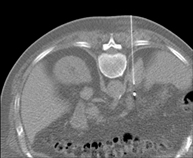

- PAAF (Punción) Abdominal guiada por TC

Consiste en obtener una muestra de tejido de una determinada lesión localizada en la cavidad abdominal. Para ello se administra anestesia local sobre la zona de la punción, la cual se realiza con agujas de fino calibre. Todo el procedimiento se realiza controlado con imágenes obtenidas por Tomografía Computarizada (TC) en varios momentos de la punción, mediante el uso de un equipo de Fluroscopia-TC. Tras la prueba, el paciente permanece unas horas hospitalizado para controlar su evolución. Es necesario aportar pruebas de coagulación antes de la punción.

- Biopsia abdominal guiada por TC

Consiste en obtener una muestra de tejido de una determinada lesión localizada en la cavidad abdominal. En ocasiones se realiza bajo sedación, con la ayuda del equipo de anestesia. Se utilizan agujas que permiten la obtención de un cilindro de la lesión a estudiar, que se enviará a Anatomía Patológica para su análisis histológico. Todo el procedimiento se realiza controlado con imágenes obtenidas por Tomografía Computarizada (TC) en varios momentos de la biopsia, mediante el empleo de Fluoroscopia-TC. Tras la prueba, el paciente permanece hospitalizado para controlar su evolución. Es necesario aportar pruebas de coagulación antes de la punción.

Consiste en obtener una muestra de tejido de una determinada lesión localizada en la cavidad abdominal. Para ello se administra anestesia local sobre la zona de la punción, la cual se realiza con agujas de fino calibre. Todo el procedimiento se realiza controlado con imágenes obtenidas por Tomografía Computarizada (TC) en varios momentos de la punción, mediante el empleo de Fluoroscopia-TC. Tras la prueba, el paciente permanece unas horas hospitalizado para controlar su evolución. Es necesario aportar pruebas de coagulación antes de la prueba.